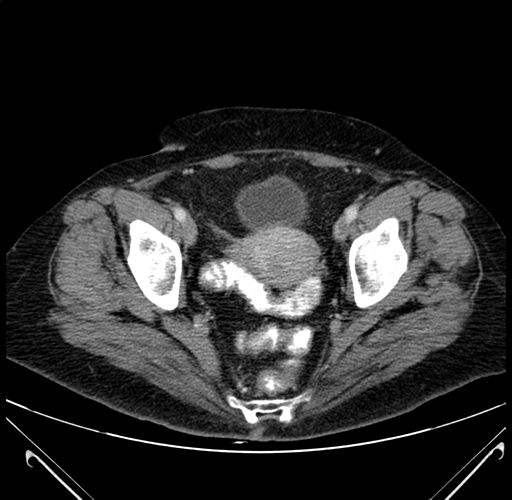

Axial Venous